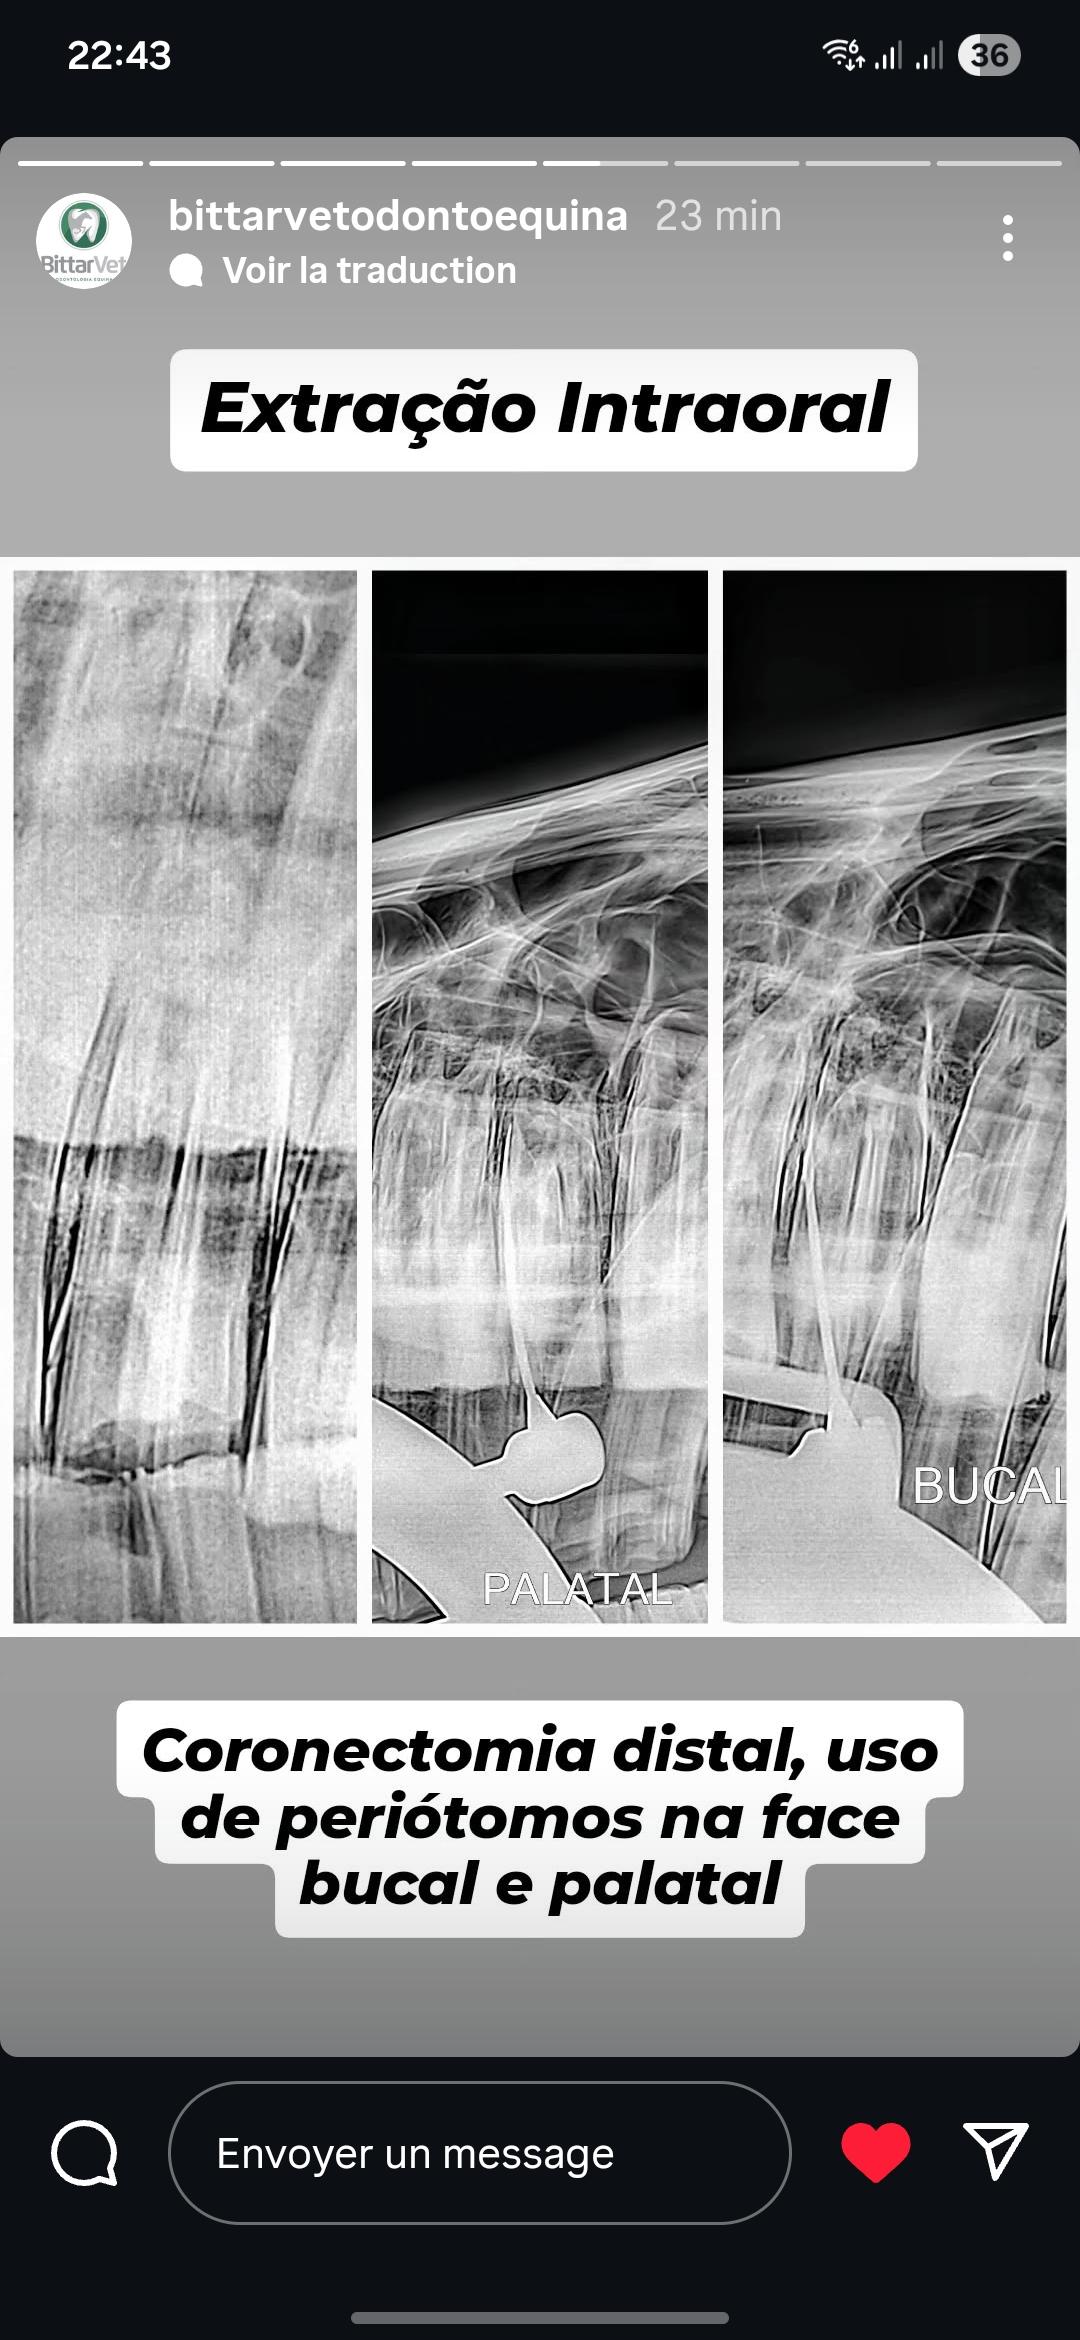

Periotome sind das erste Instrument, das bei intraoralen Zahnextraktionen zum Einsatz kommt, um Zugang zum Gingivabereich zu schaffen. Sie werden zunächst in den Gingivalsulkus eingeführt, um die marginale Gingiva von der klinischen Zahnkrone zu lösen. Anschließend werden sie zwischen der Reservekrone und dem Alveolarknochen eingesetzt, um die parodontalen Ligamente zu durchtrennen.

Für eine effektive Anwendung sollten die Klingen in apikaler Richtung eingeführt werden. Seitliche Bewegungen in bukkal-lingualer Richtung sind zu vermeiden.